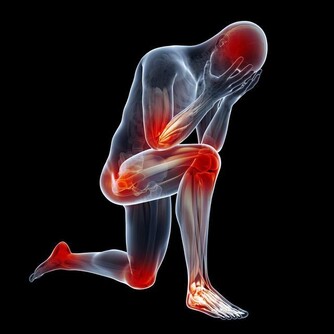

單手“四點”抓揉法

取穴:梁丘穴、四海穴、外膝眼穴、內膝眼穴

按摩手法

拇指按血海穴上,食指和無名指分別按在外膝眼穴和內膝眼穴上。

中指按在壁韌帶上,小手指按在梁丘穴上。

向上抓取,不是按揉,不要畫圈,每次向上抓取5-6分鐘即可。

特別注意

女性更年期前後,體內雌激素水平發生變化。雌激素分泌減少後,會導致女性的軟骨質量變差,更易出現髕骨軟化症。

所以女性朋友更應該注意膝關節的保養,出現疼痛不適等症狀後應引起自身的重視,及時就醫。治療及時、恰當,可大大延長膝關節的使用壽命。